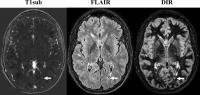

Axial MR Images Obtained in 32-Year-Old Woman with Relapsing-Remitting Multiple Sclerosis (IMAGE)

Images were obtained with subtraction of unenhanced T1-weighted MR image from contrast-enhanced MR image (T1sub), fluid-attenuated inversion recovery (FLAIR), and double inversion recovery (DIR). The new lesion (arrow), a small, subcortical lesion in right parietal lobe, is seen only on contrast-enhanced image; it was overlooked on DIR and FLAIR images. Note that there are several other new or enlarged lesions that can be seen on nonenhanced images.